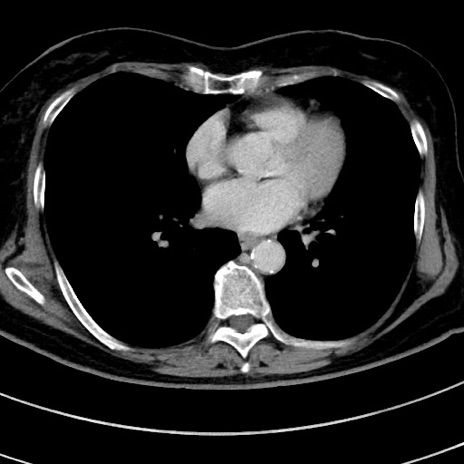

症例9(横断像)

【症例】 60歳代女性

【主訴】むかつき、みぞおちの痛み

【現病歴】3日前よりむかつきがあり、食事がとれない。

【既往歴】糖尿病

【身体所見】発熱なし、心窩部圧痛軽度あるも、腹膜刺激症状なし。

【データ】WBC 7400、CRP 1.92